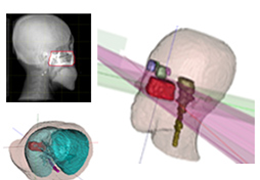

Segmentation

Segmentation of tissue (e.g., isolating the brain, differentiating gray and white matter) is performed using region-growing methods, filter operations as well as the application of 3D templates. Using the mouse it is very easy to explore a 3D volume with superimposed pseudocolor-coded statistical maps in a four-window representation showing a sagittal, coronal, transversal and oblique section. Based on a (segmented) 3D data set a three-dimensional reconstruction of the subjects' head and brain can be calculated and displayed from any specified viewpoint using volume or surface rendering.

Volume Rendering

Volume rendering is performed with a very fast ray casting algorithm; lightning calculations are based on Phong-shading. Surface rendering of reconstructed surfaces is performed using OpenGL. Using texture mapping, a reconstructed surface (e.g., head or brain) may be sliced in real time, showing both surface and volume data at the same time. Initial polygon meshes serve as the basis for surface finding, cortex inflation and cortex flattening computations.

Surface Reconstruction

The surface reconstruction procedure starts with a sphere (recursively tesselated icosahedron) or a rectangle, which slowly wraps around a (segmented) volume data set. In order to avoid topological defects and to let the surface smoothly grow into deep sulci, a dynamic mesh algorithm was developed which automatically invents new polygons on the fly at places where they are needed. A reconstructed cortical surface may be inflated, cut interactively and slowly unfolded minimizing areal distortions. Statistical 3D maps may be superimposed on reconstructed, inflated or flattened cortex. Signal time courses may be invoked by simply pointing to any region of a visualized surface.